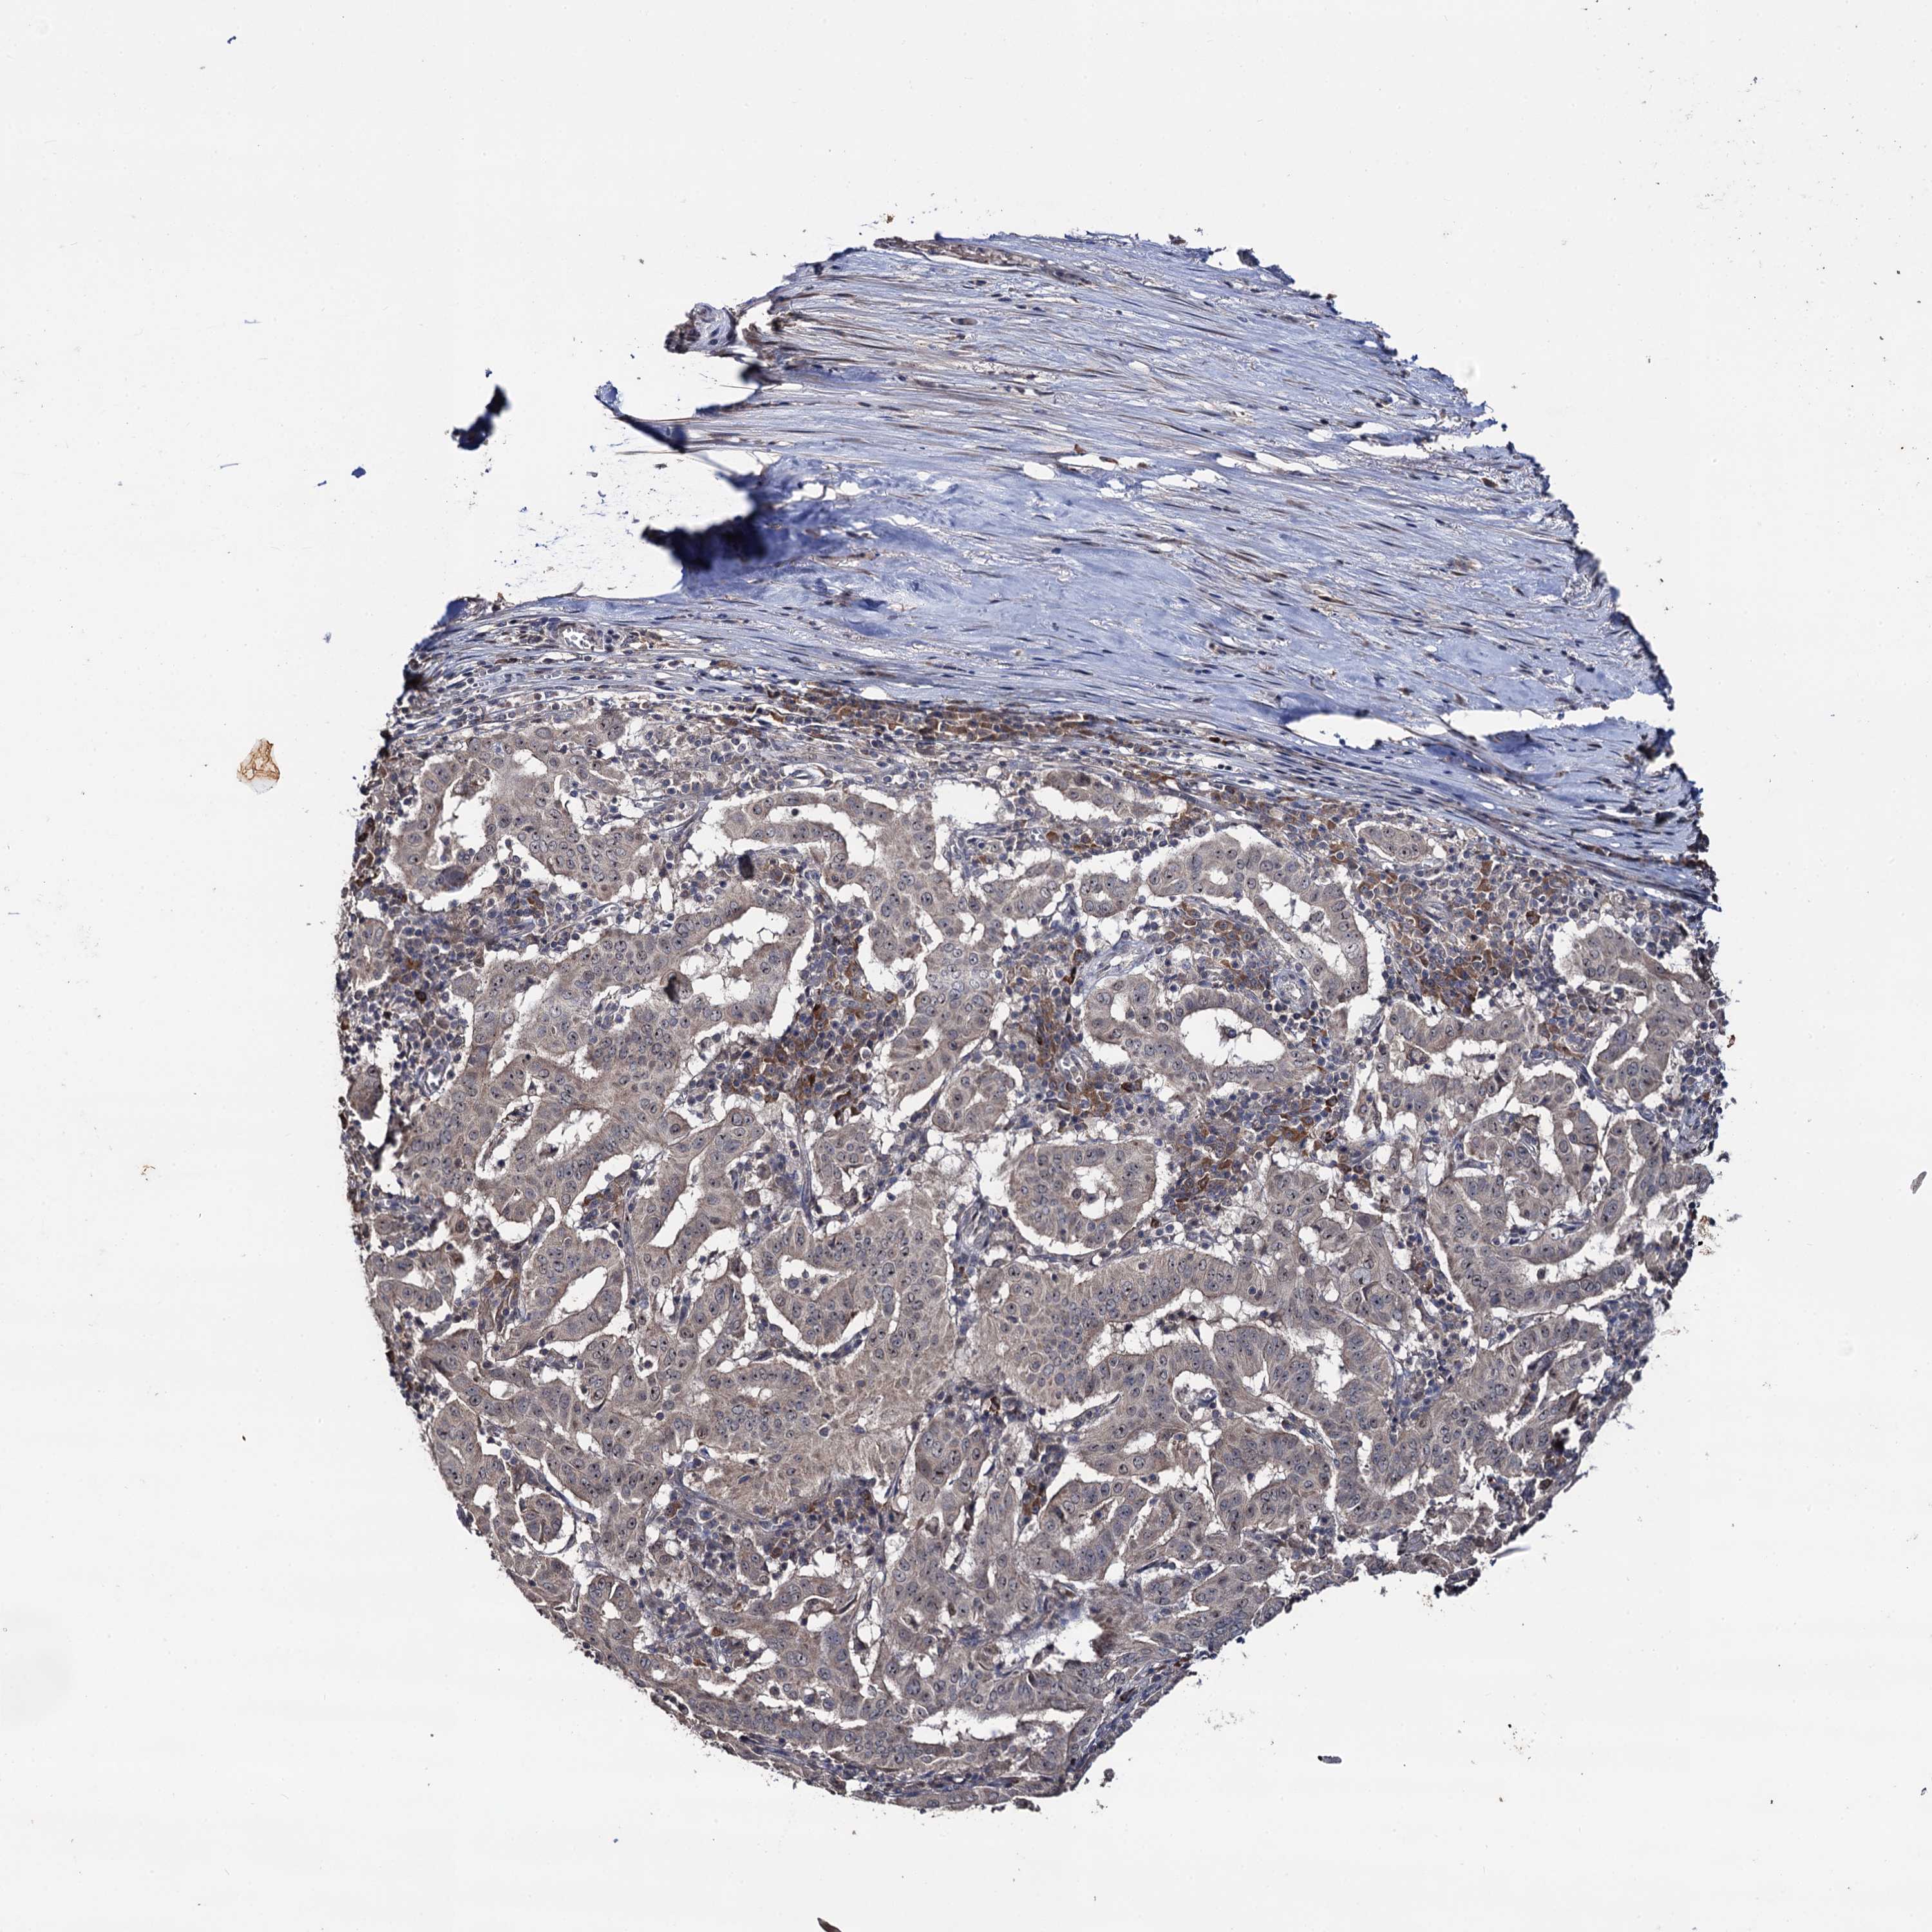

PANCREATIC CANCER - Protein expressioni

A mouse-over function shows sample information and annotation data. Click on an image to view it in a full screen mode. Samples can be filtered based on level of antibody staining by selecting one or several of the following categories: high, medium, low and not detected. The assay and annotation is described here.

Note that samples used for immunohistochemistry by the Human Protein Atlas do not correspond to samples in the TCGA dataset.

Antibody stainingi

Antibody staining in the annotated cell types in the current human tissue is reported as not detected, low, medium, or high, based on conventional immunohistochemistry profiling in selected tissues. This score is based on the combination of the staining intensity and fraction of stained cells.

Each image is clickable and will lead to virtual microscopy that enables deeper exploration of all samples and also displays staining intensity scores, fraction scores and subcellular localization as well as patient and tissue information for each sample.

Antibody HPA039318

Antibody HPA039763

Staining

High

Medium

Low

Not detected

Intensity

Strong

Moderate

Weak

Negative

Quantity

>75%

75%-25%

<25%

None

Location

Nuclear

Cytoplasmic/membranous

Cytoplasmic/membranous,nuclear

Adenocarcinoma, NOS